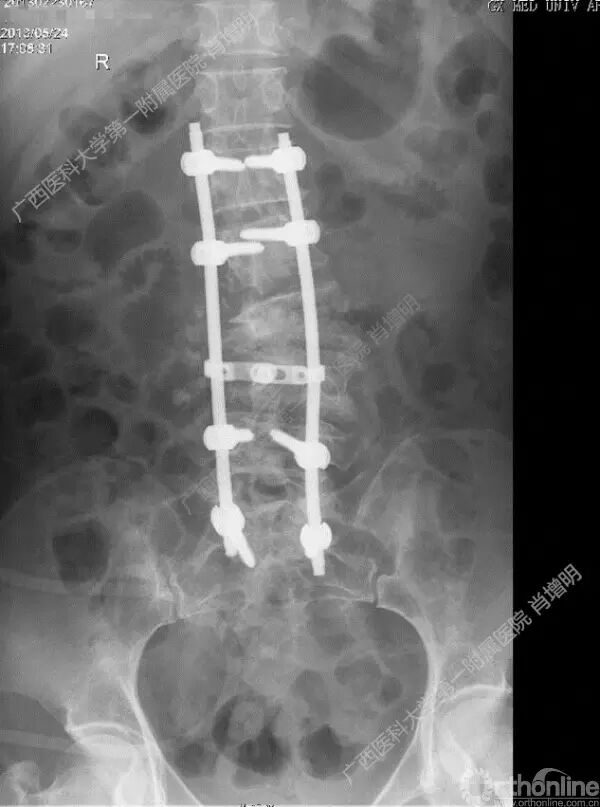

退变性脊柱侧凸是由于椎间盘退变后继发小关节退变,椎管和神经根管容积变化以及脊柱失稳,畸形等病理改变,以疼痛和神经压迫症状为主要表现的常见疾病。

退变性脊柱侧凸多发于50岁以上的中老年群体,是现代常见的老年疾病。多年来,针对该病的临床研究一直没有停步,广西医科大学第一附属医院肖增明教授细致地介绍了该病的诊疗进展。